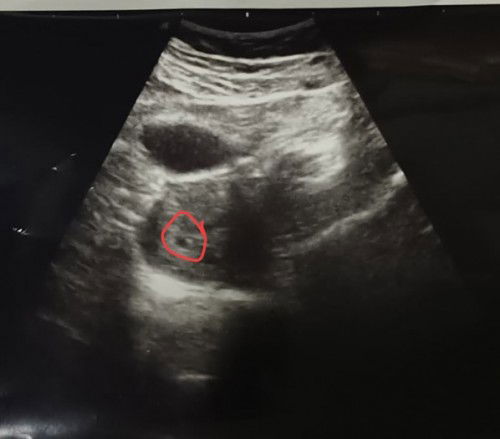

มีเลือดไหลออดจากช่องคลอด แดงสด2วันแล้วค่ะ ตอนนี้อยู่ตจว.เมื่อวานไปหาหมอ พาเข้าฉุกเฉิน ไม่เจอหมอเฉพาะทาง หมอห้องฉุกเฉินซาวด์ให้ เจอถุงตั้งครรภ์ แต่บอกว่า ถ้ายังไหลอีก อีก2อาทิตย์ให้ตรวจใหม่ ถ้า2ขีด คือยังอยู่ ถ้าขีดเดียวคือ หลุดไปแล้ว พอเราถามเรื่องฉีดยากันแท้ง ก็มาย้อนเราว่าฉีดที่ไหนละ ถ้าเขาจะอยู่ก็คืออยู่ ไม่อยากอยู่ก็คือไป อายุครรภ์แค่นี้ ถ้าหลุด ก็ไม่มีปัญหาอะไร คือเราฟังแล้วหดหู่มาก เมื่อวานกลับจากหาหมอ เลยซื้อมาตรวจ ยัง2ขีดอยู่ค่ะ วันนี้ไหลอีก เรานอนไม่หลับเลยค่ะ ต้องทำยังไงดีค่ะ #ขอคำแนนำหน่อยค่ะ#ขอบคุณล่วงหน้านะคะ